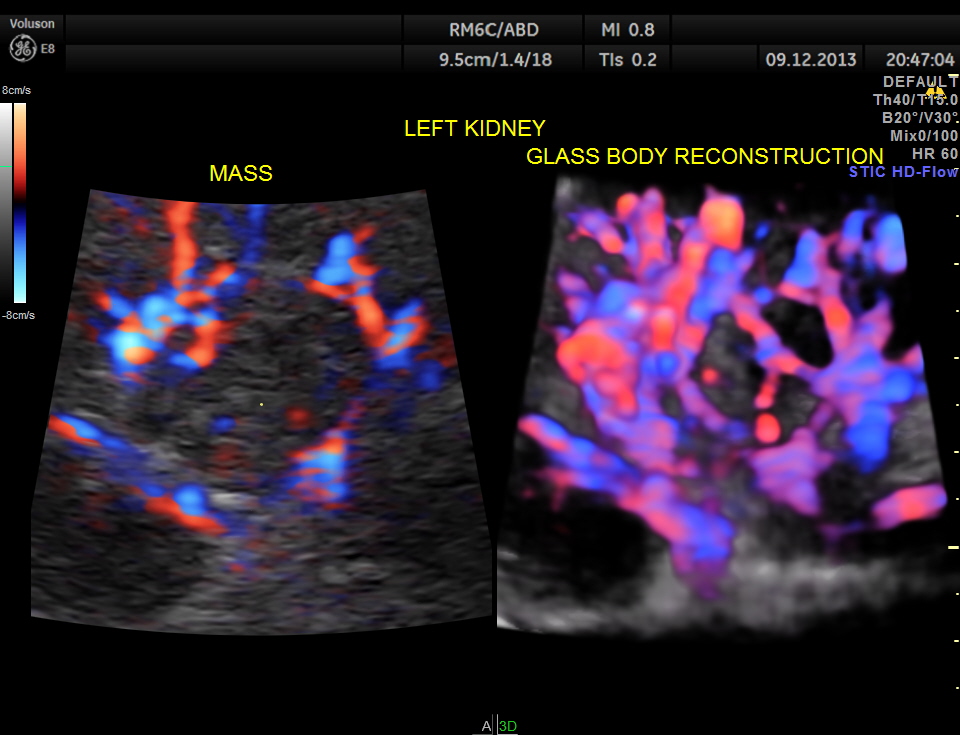

GLASS BODY RECONSTRUCTION IS GIVEN BELOW.

INCREASED VASCULARITY OF THE MASS IS WELL MADE OUT IN THIS GLASS BODY RECONSTRUCTION.